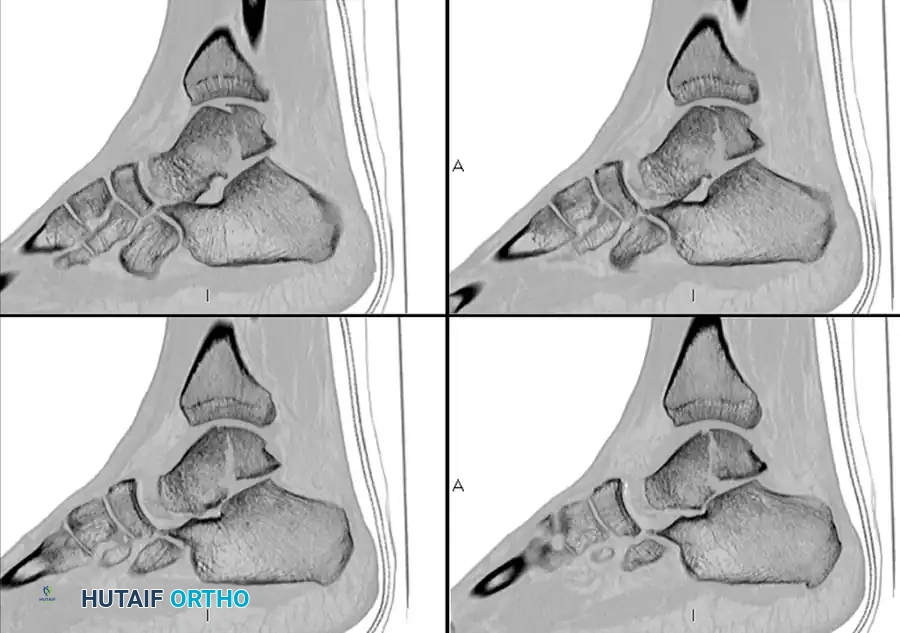

The Critical Role of Computed Tomography (CT)

The importance of obtaining a CT scan after reduction of the subtalar dislocation cannot be overstated. Patients who sustain a subtalar dislocation frequently have additional osteochondral abnormalities that are initially missed on plain radiographs.

Surgical Warning: We routinely use CT for the post-reduction evaluation of these injuries. Up to 60% of peritalar dislocations have associated fractures (e.g., talar head, navicular, calcaneal facets) that require operative treatment because of intraarticular displacement or fragments blocking congruent reduction.

After closed reduction of the dislocation, no fracture is apparent on the standard lateral radiograph.

CT scans of the same patient, however, clearly demonstrate an intraarticular talar fracture requiring fixation.